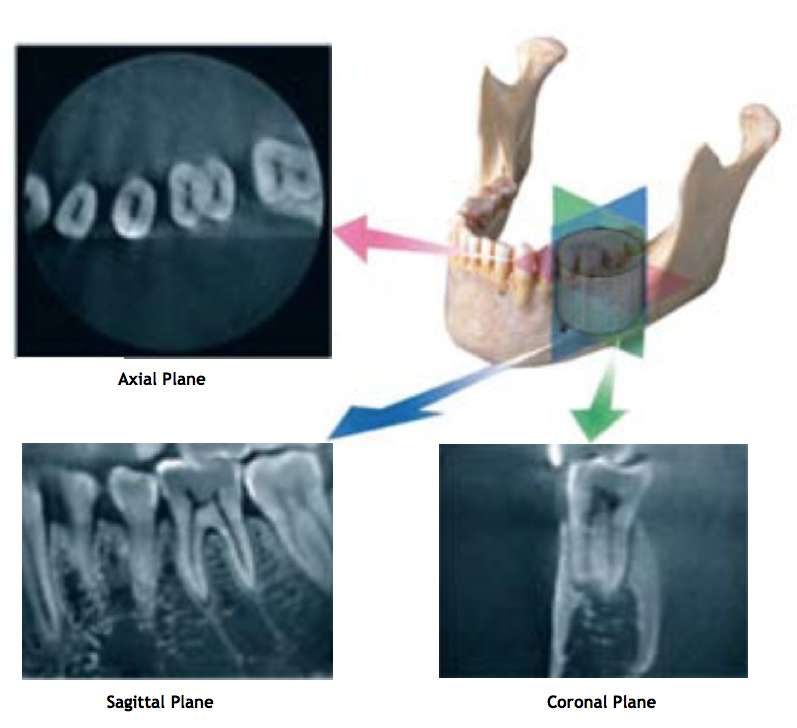

Perhaps the most important advantage of CBCT in endodontics is that it demonstrates anatomic features in three dimensions that intraoral and panoramic images cannot. CBCT units reconstruct the data to provide interrelational images in three orthogonal planes (axial, sagittal and coronal).

Fig 4. Representation of 3-D view of the lower left quadrant, tooth #19; axial, sagittal and coronal orthogonal planes. (2)